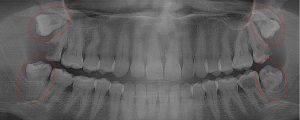

This 48 year old patient had all four 3rd molars extracted in his late 20’s. All four sites healed poorly and chronically infected bony defects remained. The upper right 2nd molar was extracted two years ago as a result of this chronic infection. The upper left 2nd molar must now be extracted because of a chronic periodontal infection moving around that tooth. Both lower molars are chronically infected and have a poor prognosis.